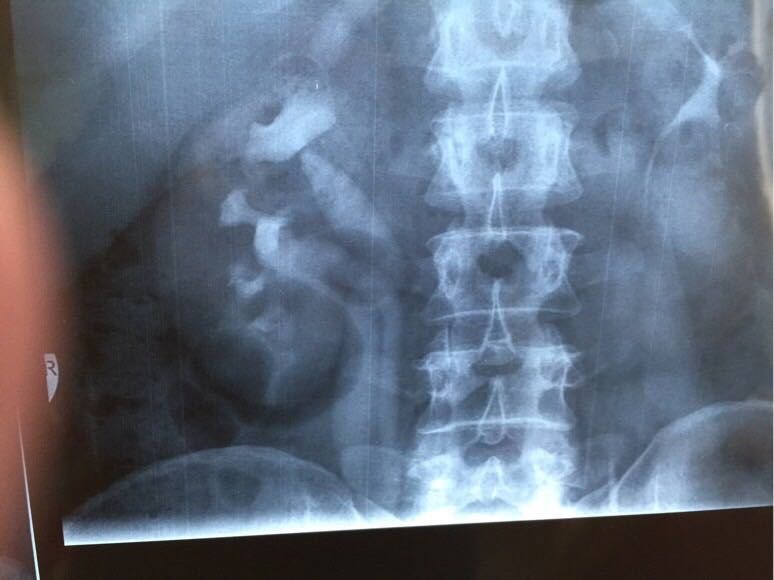

辅助检查超声:左重复肾畸形,左上半肾扩张,左输尿管开口囊肿;逆行肾盂造影:左侧上肾盂肾盏扩张积水明显,肾盏杯口消失,左输尿管下端扩张积水;CT:左重复肾双输尿管,左上半肾积水(如图);MRI:左重复肾伴左上半肾重度积水,引流左上半肾的输尿管中下段明显扩张。